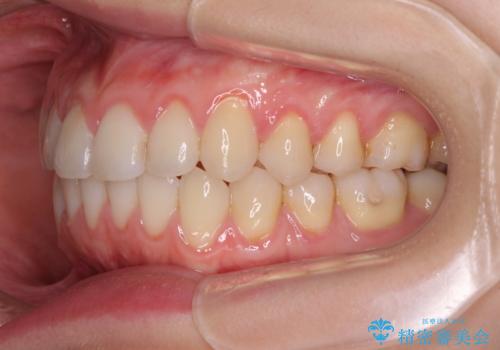

- 上下前歯のデコボコを気にして来院された患者様です。

インビザラインによる上下歯列の側方拡大と後方移動、IPR(歯と歯の間を削る)にるスペースの獲得により歯列を整えることとしました。

1日22時間の装着時間をしっかり守ってくださったので、予定していた1年よりも早く治療を終えることができました。

インビザライン矯正特有の奥歯がしっかりと咬合しない感覚も改善され、大変満足していただきました。